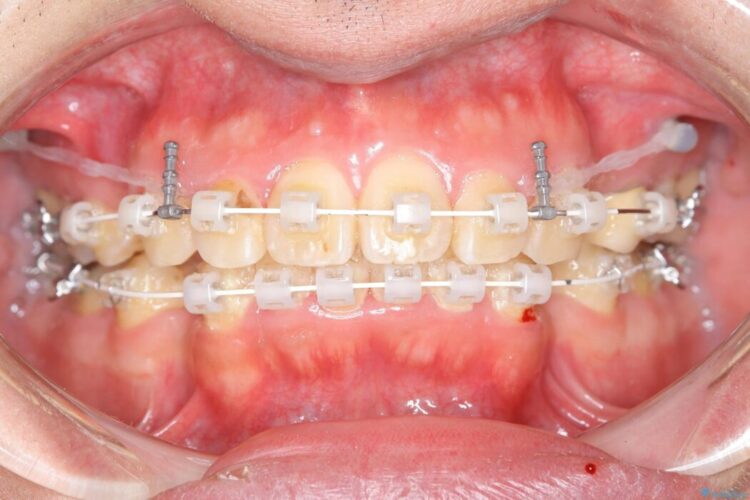

抜歯でスペースができるため、歯の移動量が多いことから表側ワイヤー矯正装置で治療を行いました。

ワイヤー矯正、マウスピース矯正、それぞれの特性、得意な治療がありますので、患者様の状態に合わせた治療器具の選択が大事となります。